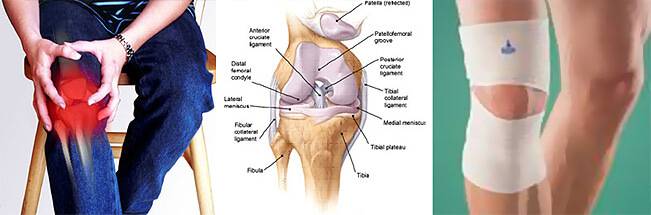

Возможные причины болей в ноге ниже колена и рекомендации